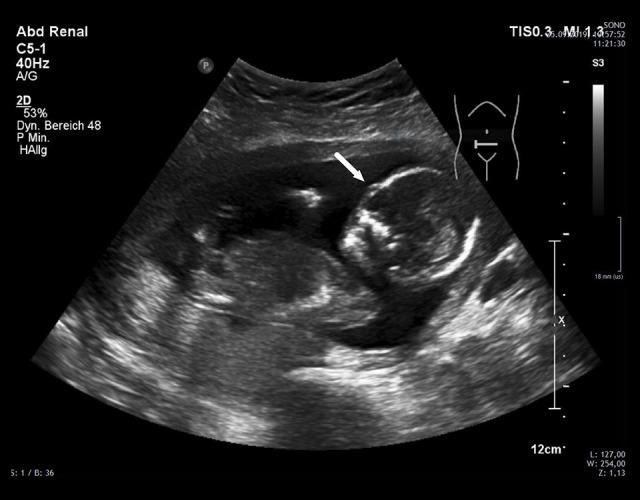

BACKGROUND There has been, to our knowledge, no reports on LifeCycle Pharma tacrolimus (LCPT) taken during pregnancy after simultaneous pancreas-kidney transplantation (SPK). Here, we report a 25-year-old female SPK recipient who gave birth to a healthy infant in posttransplant month 32. We analyzed the long-term graft function, obstetric/neonatal course, LCPT dosage, tacrolimus (TAC) levels, concomitant medication, and complications. CASE REPORT Her medical history consisted of type 1 diabetes with chronic nephropathy, arterial hypertension, and atypical haemolytic uremic syndrome with critical deterioration of her general condition requiring clinically indicated early termination of her first pregnancy prior to SPK. SPK was performed according to surgical standards. The immunosuppressive prophylaxis consisted of thymoglobulin, mycophenolate mofetil, standard TAC formulation, and steroids. Due to rapid TAC metabolism, the patient was converted from a standard TAC formulation to LCPT in the first month posttransplant. Her long-term immunosuppression, including the obstetric and peripartal course, consisted of LCPT, prednisolone, and azathioprine. She was normotensive without antihypertensive medication and maintained excellent function of both grafts during the observation period of 48 months posttransplant. All (mostly infectious) complications were reversible, especially temporary polyoma viremia within normal renal function, and 2 episodes of urosepsis. No relapse of her pretransplant episode of atypical haemolytic uremic syndrome occurred posttransplant. Her child is in good health at the age of 12 months without any malformations. CONCLUSIONS This case suggests that pregnancy after SPK under LCPT is feasible. Further studies are needed to expand the empirical knowledge surrounding tacrolimus.